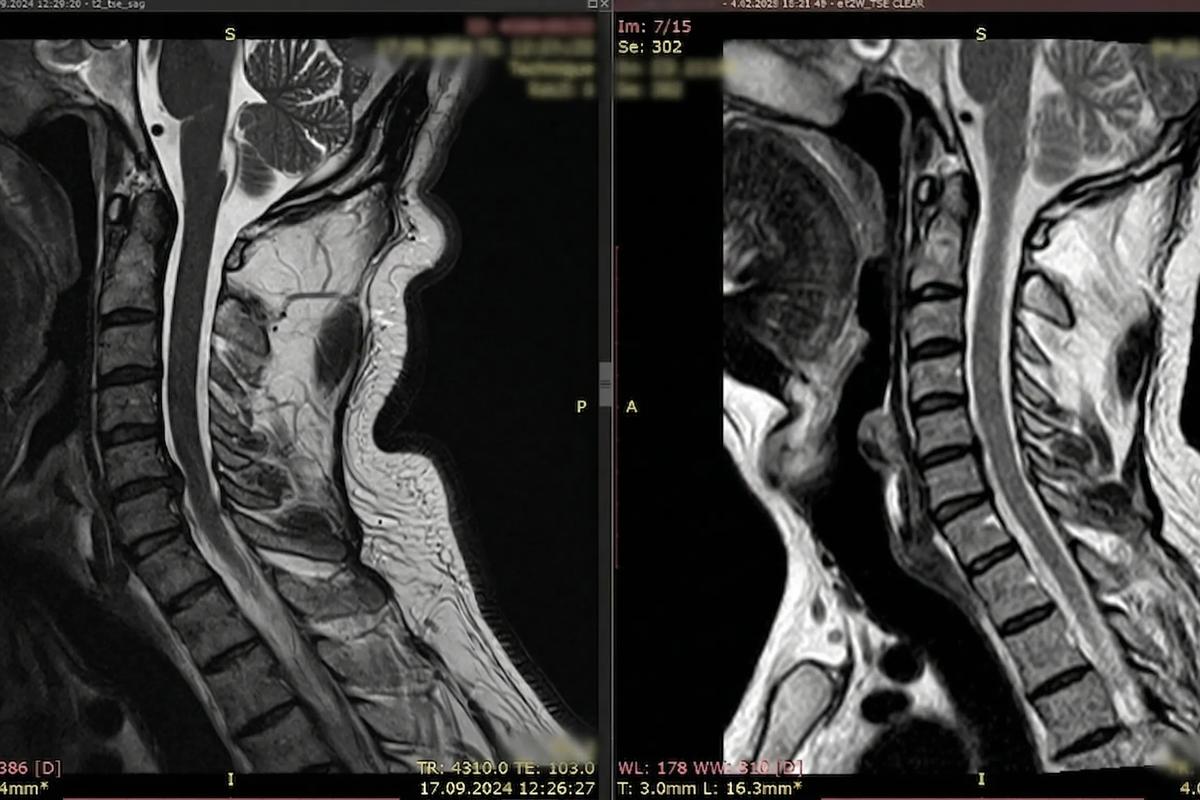

التشخيص بالذكاء الاصطناعي والرنين المغناطيسي

لا نعتمد على الفحص السريري وحده. نستخدم برمجيات تحليل الصور المتقدمة لتحديد نسبة التضيق في القناة الشوكية بدقة تصل إلى 99%.

خلف كل صورة رنين مغناطيسي قصة إنسان استعاد قدرته على النوم والعمل بدون ألم. في مركز DRFK، نفخر بمعدلات نجاح تتجاوز 95% في حالات علاج آلام الرقبة والديسك العنقي.